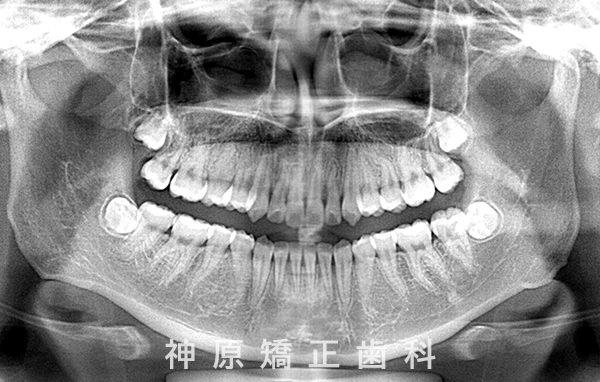

開窓牽引開始時

上のあご(上顎)の右側の犬歯について、歯の生えてくる方向に異常が見られました。そのため、歯ぐきを一部開いて、犬歯を正しい位置に引っ張り出す「開窓牽引」という処置を行いました。